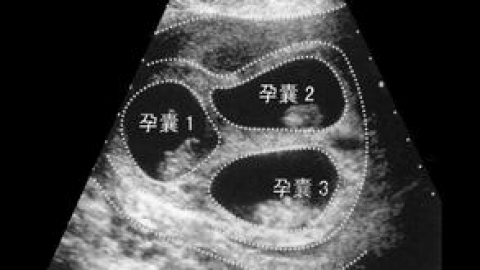

双(多)胎妊娠的几件“P”事

3%,多胎妊娠脑瘫发生率比单胎妊娠高5~10倍。双...